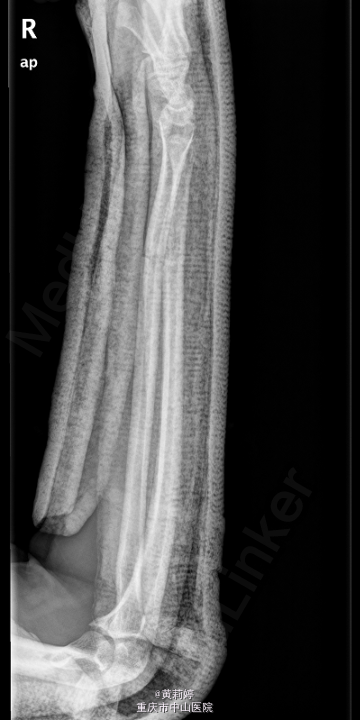

患者,男,17岁,因“摔伤致右侧前臂及腕部胀痛伴活动受限1天”入院。

右前臂石膏托固定,右前臂肿胀,畸形,压痛明显,右腕活动障碍,手指血运好,活动可,其余肢体无明显异常,神经系统检查无殊。我院右尺桡骨正侧位片示:右尺桡骨远段骨折、石膏外固定改变。我院右腕关节CT示:右尺桡骨远段骨折、石膏外固定术后。